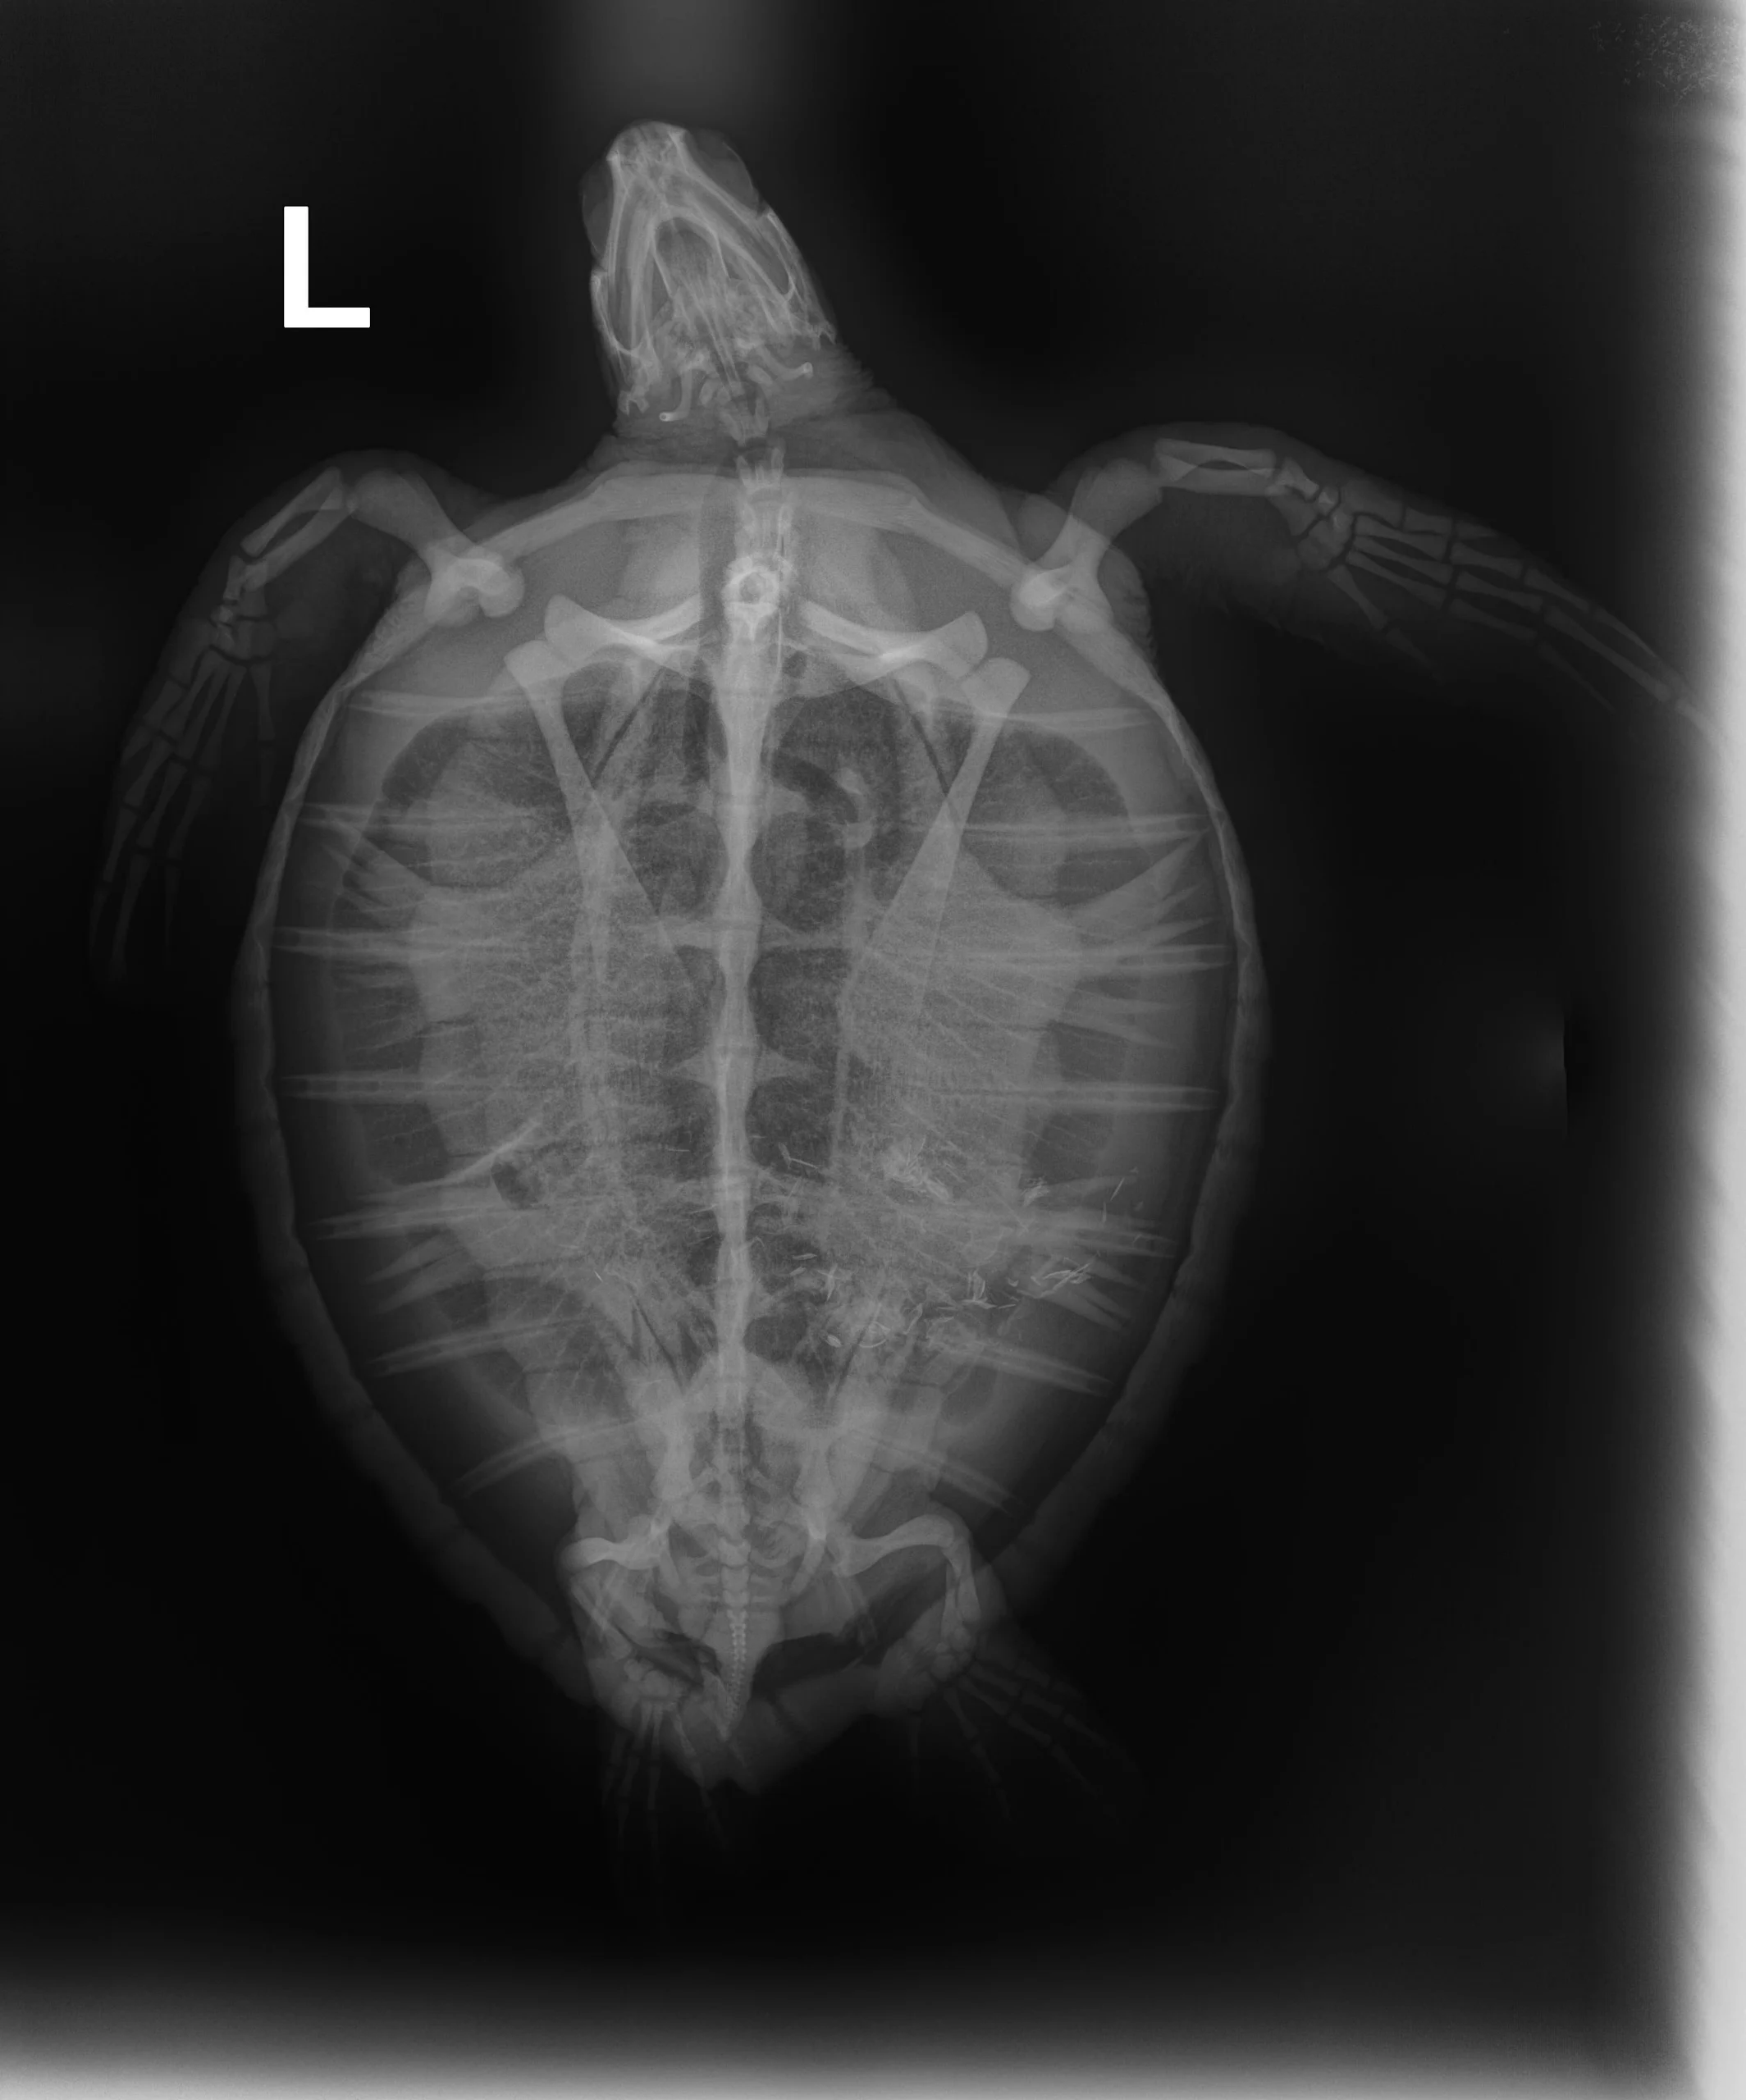

2.05 kg juvenile Atlantic Green sea turtle

Patient Injuries

External Carapace Notes: Minor abrasions, old healed fracture to the upper right side carapace, abrasions on the left side marginal scutes on carapace

Plastron: Minor plastron abrasions

External Wounds: old healed fracture to the upper right side carapace